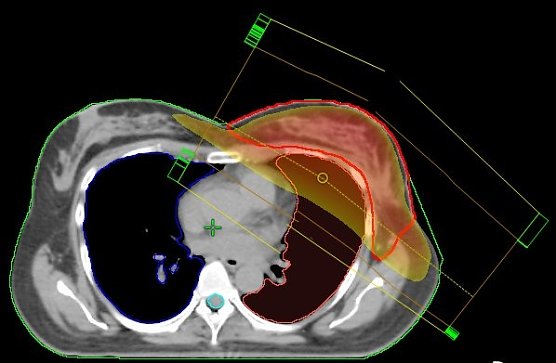

Stehfeldtechnik (Foto: Südharz Klinikum) Stehfeldtechnik (Foto: Südharz Klinikum)

Normal: Stehfeldtechnik mit 2 Feldern (Standardtechnik); der Hochdosisbereich erfasst nicht nur das Zielvolumen (rote Kontur), sondern auch die umgebenden Risikoorgane (Lunge und Herzkranzgefäße), was zu Nebenwirkungen führen kann